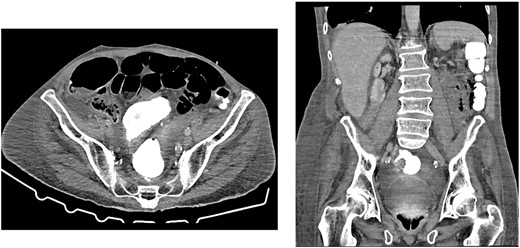

CT showing resolution of the tension pneumoperitoneum post pig-tail insertion and anastomotic integrity—no leakage of contrast

His abdomen was emergently decompressed over the evening; however, within 12 h, the pneumoperitoneum had recurred. We then inserted a 14.0 Fr, 29 cm pig-tail catheter at bedside (Fig. 4). It was then connected to an intercostal catheter (ICC) drain. Immediately, a gush of air was released, there was bubbling in his chest drain and his abdomen immediately became less tense. As no obvious site of viscous perforation was identified on imaging, we decided to explore other causes of pneumoperitoneum. These included severe COPD, broncho-peritoneal fistula, bullous emphysema and anastomotic leak [5–7]. Cardiothoracic surgeons (CTS) were consulted regarding potential thoracic causes of his pneumoperitoneum given his background of severe emphysema but was deemed highly unlikely by both the CTS and radiologists as his CT chest did not show a large bullae or broncho-peritoneal fistula and he was not mechanically ventilated. A CT with rectal contrast was performed to exclude anastomotic leak from the rectal anastomosis, and there was no evidence of contrast extravasation into the peritoneum at the anastomosis site (Fig. 5). The pig-tail catheter was in place for 3 days and then clamped for two days without any re-accumulation of the pneumoperitoneum, the pigtail was removed and the patient was discharged without further complications.